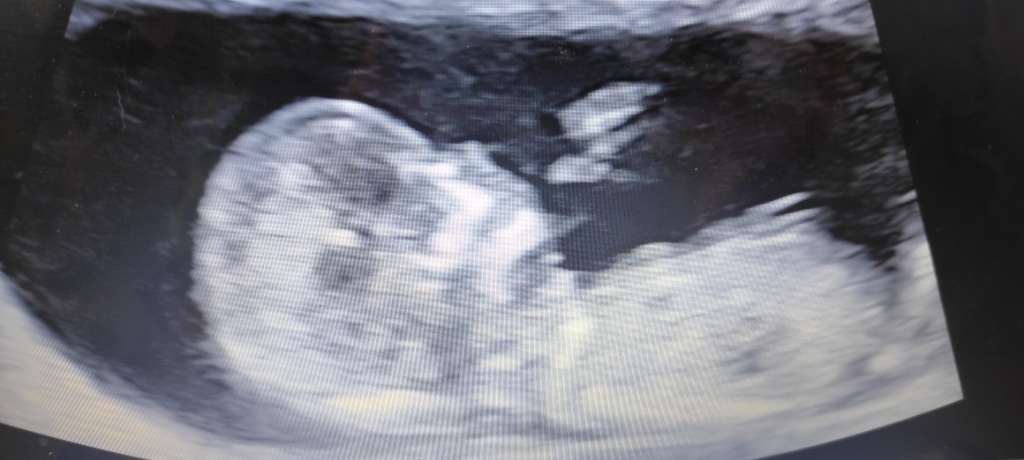

Dzidzia z rana 😁 wszystko super wyszlo

Załączniki

• f7193688-1c33-45c3-ab62-bb8afe7f07f0.jpg

f7193688-1c33-45c3-ab62-bb8afe7f07f0.jpg

11,4 KB · Wyświetleń: 109